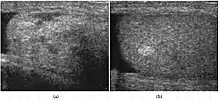

Teratoma Although teratoma is the second most common testicular tumor in children, it affects all age groups. Mature teratoma in children is often benign, but teratoma in adults, regardless of age, should be considered malignant. Teratomas are composed of all three germ cell layers, i.e. endoderm, mesoderm and ectoderm. At ultrasound, teratomas generally form well-circumscribed complex masses. Echogenic foci representing calcification, cartilage, immature bone and fibrosis are commonly seen [Fig. 5]. Cysts are also a common feature and depending on the contents of the cysts i.e. serous, mucoid or keratinous fluid, it may present as anechoic or complex structure [Fig. 6].

Fig. 5. Teratoma. A plaque-like calcification with acoustic shadow is seen in the testis.![Fig. 6. Mature cystic teratoma. (a) Composite Image. Mature cystic teratoma in a 29-year-old man. Longitudinal sonography image of the right testis shows a multilocular cystic mass. (b) Mature cystic teratoma in a 6-year-old boy. Longitudinal sonography of the right testis shows a cystic mass containing calcification with no obvious acoustic shadow.[citation needed]](../I/Ultrasonographies_of_mature_cystic_teratomas.jpg.webp) Fig. 6. Mature cystic teratoma. (a) Composite Image. Mature cystic teratoma in a 29-year-old man. Longitudinal sonography image of the right testis shows a multilocular cystic mass. (b) Mature cystic teratoma in a 6-year-old boy. Longitudinal sonography of the right testis shows a cystic mass containing calcification with no obvious acoustic shadow.

Fig. 6. Mature cystic teratoma. (a) Composite Image. Mature cystic teratoma in a 29-year-old man. Longitudinal sonography image of the right testis shows a multilocular cystic mass. (b) Mature cystic teratoma in a 6-year-old boy. Longitudinal sonography of the right testis shows a cystic mass containing calcification with no obvious acoustic shadow.